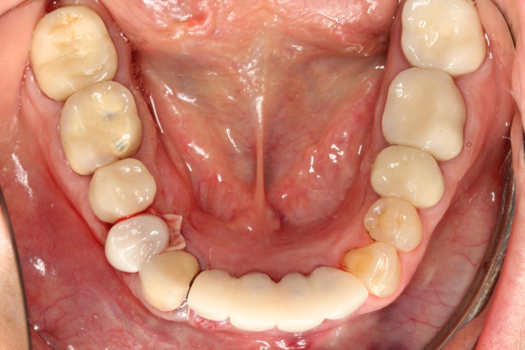

The next case follows the digital protocol for fully guided surgery and prosthetics. A CBCT radiograph, digital impression, and digital photography were the cornerstones to the success of this case. The 3D data set was electronically delivered to the dental laboratory. The data were merged and the process to develop the plan was initiated. The use of CBCT was essential in this case, particularly due to minimal space for placement of individual implants and single-unit crowns. The patient's chief concern was that she wanted to have single-unit crowns instead of fixed crown-and-bridge restorations because she was worried that she would someday find herself in an assisted-living facility; if that were to happen, she wondered, who would help floss under her bridge work? Her decision was to have single implants with individual crowns. CBCT technology is much more accurate in evaluating space maintenance and management.10 Periapicals in the past were rather close for calculating spacing; however, the CBCT identifies the buccal-lingual dimensions as well as the mesial-distal measurements. On review of the completed proposals for implant placement and provisionals, it was determined that there was sufficient spacing for implant placement to allow appropriate emergence profiles for the provisionals and then eventually the final single-unit cemented crowns. The proposal was accepted, and a 3D-printed surgical stent was fabricated, along with the PMMA provisionals (Figure 29 through Figure 35).

On the day of surgery, the plan was to extract teeth Nos. 21, 23, 24, 25, and 26, place 3.0 x 13-mm implants in the anterior region due to limited spacing, and place a 4.1 x 10-mm implant in the No. 21 extraction site. Before the extractions were performed, the No. 23 pontic was sectioned from the existing 2-unit cantilevered bridge utilizing ceramic and metal high speed rotary cutting burs ZR 6881 and H34L (Komet-USA), respectively. After removal of the pontic and extractions, the surgical guide was verified to be seating positively (Figure 36 through Figure 38). Surgical guide protocol was followed, and all implants were successfully placed and torqued to a value of greater than 35 Ncm (Figure 39 and Figure 40). All implants were placed without flapping, with the exception of No. 23. The flap was elevated to reposition lingual keratinized tissue facially for enhanced esthetic tissue profile. The implants were then prepared with a high-speed carbide bur (Komet-USA) with copious amounts of water (Figure 41 and Figure 42). The one-piece 3.0-mm diameter implant served the needs of the patient's spacing requirements. Inter-occlusal space requirements and path of draw were verified. The PMMA provisionals were air abraded and relined with crown-and-bridge material (Figure 43 through Figure 45).

Fig 42. Occlusal view of prepared implants.

Figure 42